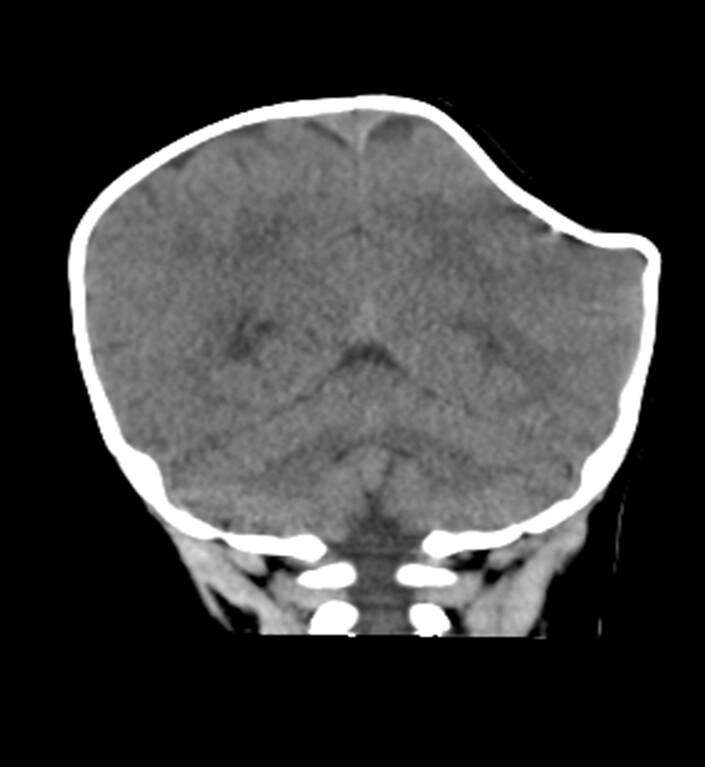

▼寶寶被送到醫院時,左側頭骨凹陷變形,右側頭顱凸起血腫,頭骨凹陷約5X5公分,血腫約5X7公分。幸好寶寶沒有顱內出血,這才保住一命。斷層檢查時,寶寶頭部的影像就像「咬了一口的蘋果」,非常嚇人。

▼院方進行開顱手術,原本想學汽車板金處理,將他頭骨凹陷的地方頂出來。但頭骨太硬,只好內外翻轉,讓他的頭部恢復原狀。手術順利完成,寶寶一周後就能康復出院。